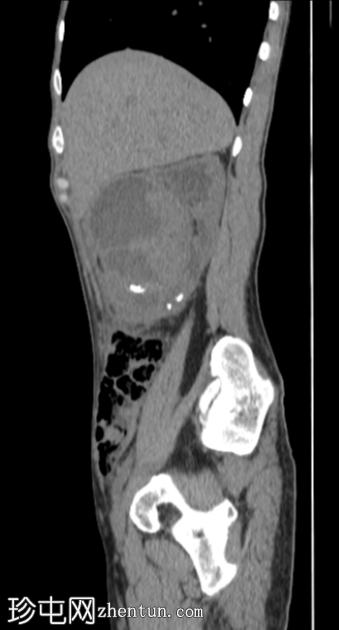

矢状位

平扫

右肾前部可见一边界清晰的外生性病变,呈异质性,包含实性及囊性成分,内部可见多发结石。肾周可见模糊影。

病变内部存在结石及肾周模糊影提示炎症性病变,可能为局灶性黄色肉芽肿性肾盂肾炎(XGP),而非肿瘤性肿块(肾细胞癌)。